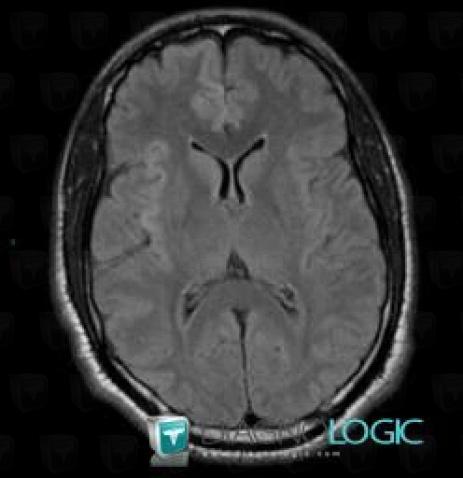

Hypoxie corticale, Région cortico sous corticale, IRM

Voici les informations spécifiques à l'image clé ci dessus:

- Diagnostic Hypoxie corticale, Localisation(s) Région cortico sous corticale, comportant les gammes Lésion corticale, Anomalie gyriforme